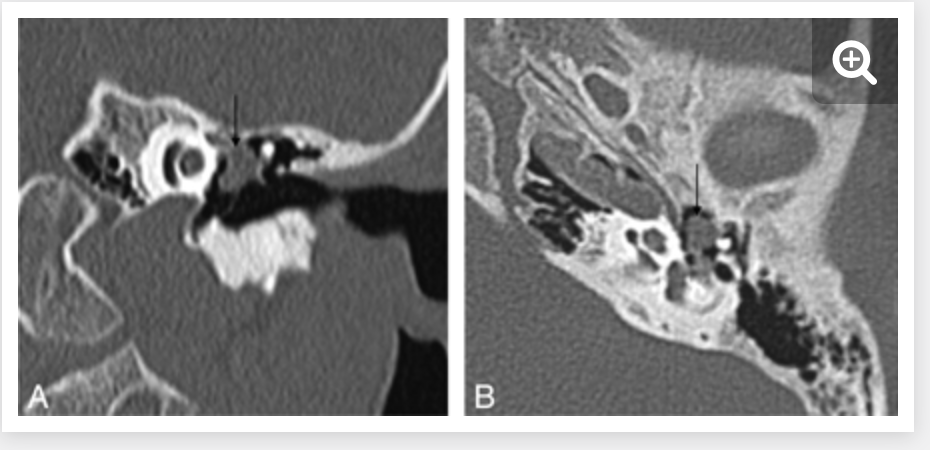

cochlear aplasia

The labyrinth is abnormal with the cochlear absent (cochlear aplasia). The vestibule, semicircular canals and ossicles are present.

Cochlear aplasia, or complete absence of the cochlea is a rare anomaly which accounts for only 3% of cochlear malformations.